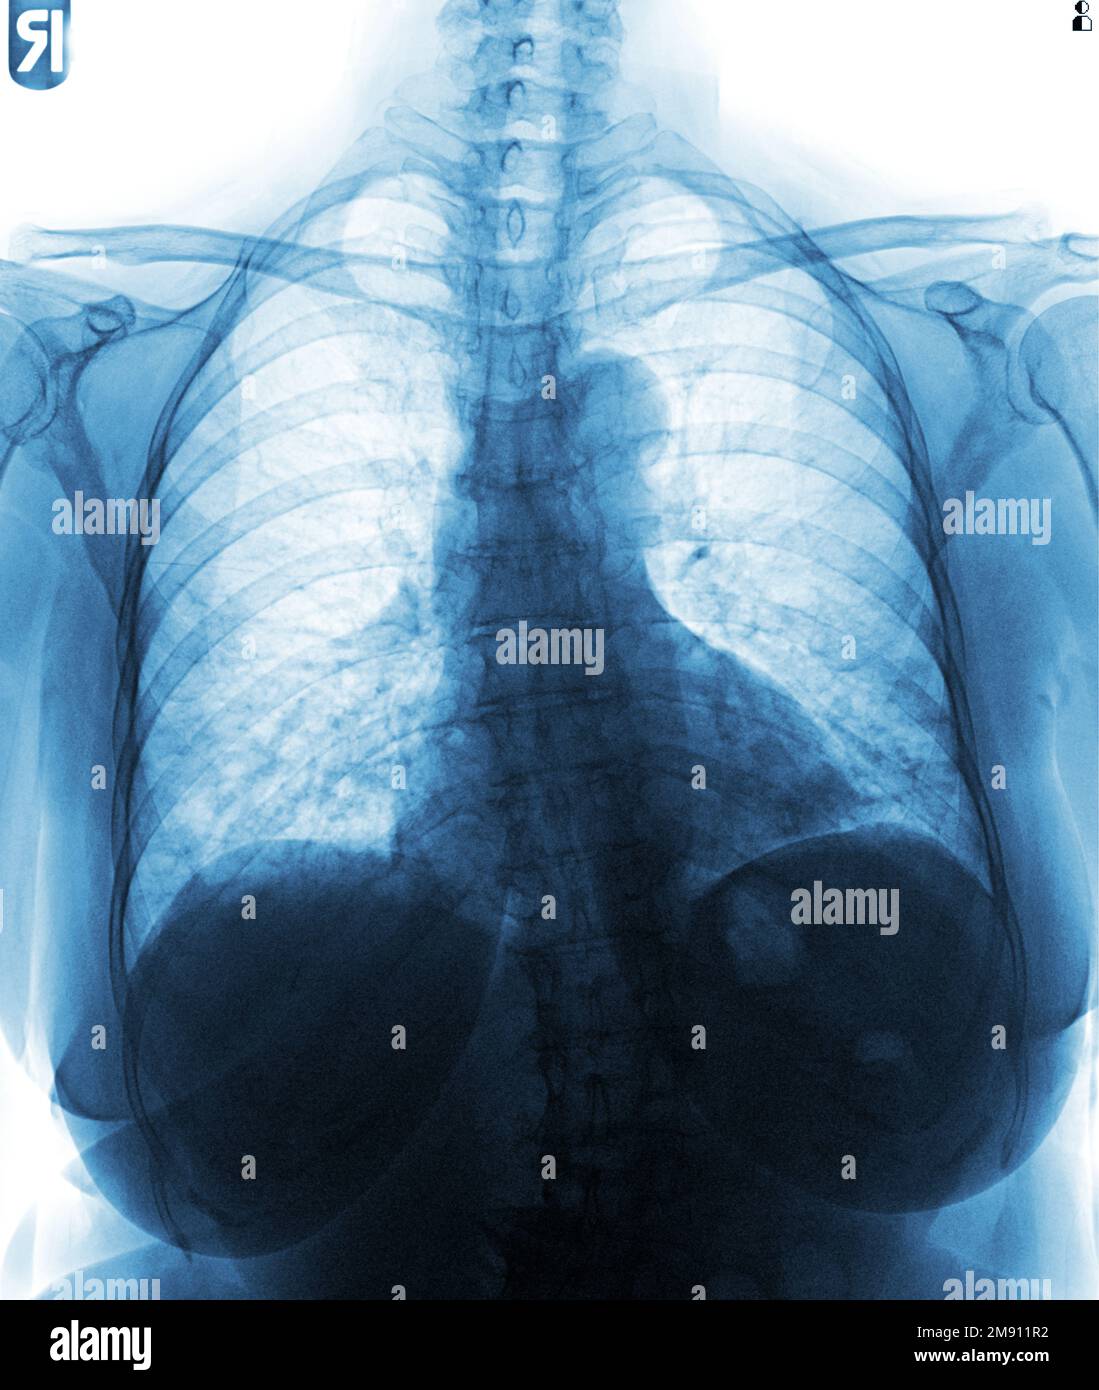

Normal Chest X Ray Male